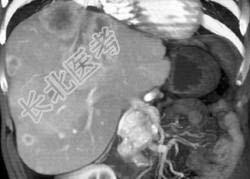

- 单项选择题男,48岁, 胃癌术后1年,未化疗, CT检查如图所示,最可能诊断为  (    )

- A、肝癌

- B、肝转移癌

- C、肝血管瘤

- D、肝脓肿

- E、肝囊肿